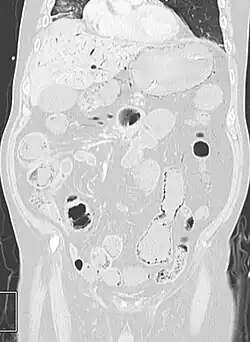

Pneumatosis intestinalis in the coronal computed tomography in lung window. It can be seen next to gas entrapment in the bowel wall and gas in the stomach wall and in numerous vessels, including the portal vein into the liver. -